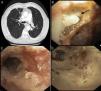

A) Pérdida de volumen del hemitórax izquierdo con estenosis del bronquio principal izquierdo y bronquiectasias en el segmento apical del LSD. B) Lesión ulcerativa para-traqueal inferior izquierda cubierta por secreción mucopurulenta (flecha). C) Mucosa seudomembranosa en el tercio distal de la tráquea y BPI. D) Dilatación con catéter balón de la estenosis del BPI.

Varón de 71 años de edad con antecedentes de adenocarcinoma pulmonar diagnosticado y tratado en el año 2006 con QT y RT concomitante, consultó en febrero de 2015 por infecciones respiratorias de repetición. La TC toracoabdominal (fig. 1A) demostró una estenosis del bronquio principal izquierdo. La broncoscopia flexible mostró: a) lesión ulcerativa para-traqueal inferior izquierda cubierta de secreción mucopurulenta (fig. 1B), y b) mucosa seudomembranosa en el tercio distal de la tráquea y BPI (fig. 1C). Se realizó dilatación efectiva con catéter balón (CRE™ Pulmonary; Boston Scientific) del BPI (fig. 1D). Se realizó un aspirado traqueobronquial en el bronquio principal izquierdo y se tomaron biopsias endobronquiales de las lesiones ulcerativas descritas. La biopsia reveló la presencia de hifas bifurcadas en ángulos de 45° con tinción positiva por el método histoquímico de Grocott confirmando el diagnóstico de Aspergillus fumigatus. El cultivo del aspirado traqueobronquial fue positivo para Aspergillus fumigatus.